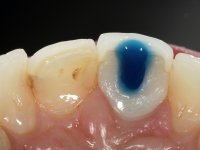

After performing an impression of the implant and making the models, we tested several rehabilitative options with the help of the implant brand planning kit. None proved capable. In this sense and as a resource solution, an innovative solution was proposed. It was proposed to make a milled Zr abutment with an appropriate design to receive a veneer that would hide the screw access hole. The veneer itself had a ceramic-coated Zr infrastructure. The goal was to achieve retention and strength by screwing the abutment and aesthetically solve the case with the veneer.

After the impression of the implant using a double-mix technique with double viscosity and the collection of shape and color information by the ceramist, we proceed with the work. In the model, a syn octa was placed over the implant, and a screw was placed on it to assess its emergence in relation to the incisal edge. Then, an adequate emergence profile in the artificial gingiva was prepared. A abutment with characteristics suitable for overbite and simultaneously capable of receiving a veneer was waxed on top of this scenario. This waxing gave rise to the manual milling of a very personalized abutment. An infrastructure in Zr was also made for the veneer with a very great adaptation to the abutment. On this infrastructure ceramics were placed. Ceramic fluorescence sought to compensate for the lack of fluorescence that Zr had and obviously further customize the aesthetics. The adhesive bridge was removed and the definitive work was placed. The syn octa was initially tightened with 35 N to the implant and then the Zr abutment was tightened over the syn octa with 15 N. The access hole was plugged and then the veneer was cemented with resin-reinforced glass ionomer. After 15 years, the patient returned to the consultation with tooth mobility. Fortunately, nowadays we have the possibility of having dynamic tightening wrenches that allow tightening screws with greater inclinations. An access cavity was made without damaging the incisal edge of the veneer. Tightening was done with a dynamic wrench with 15 N torque. The hole was covered with Teflon and filled with composite resin. This solution allowed the problem to be solved in a simple and economical way.